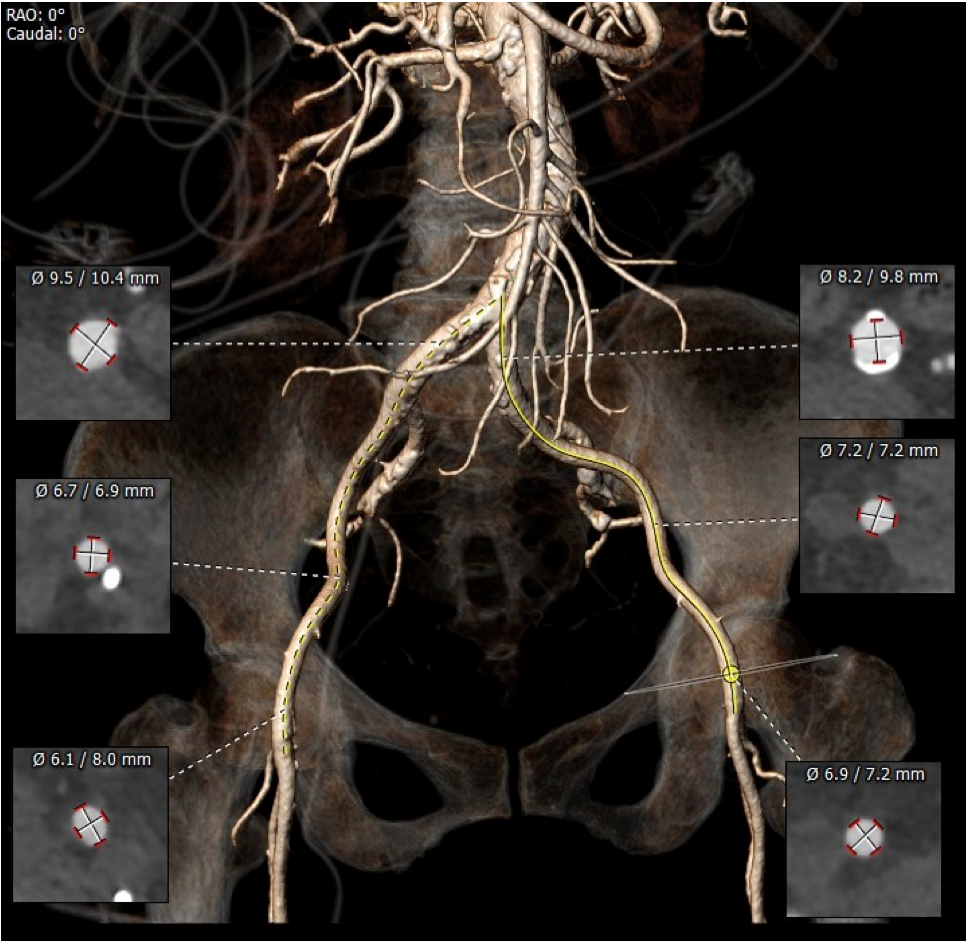

CT 数据显示该患者为Type1型二叶式主动脉瓣

主动脉瓣瓣环周长76.8mm,周长径24.5mm;

LVOT 周长 86.1mm,周长径27.4mm;

SOV:32.3mm*34.5mm*33.7mm;

STJ 周长 100.6mm;

瓣叶严重粘连增厚,瓣叶钙化明显,HU850:1448.3mm³。

左冠开口高度8.6mm,右冠开口高度15.0mm,左冠高度偏低,左冠瓣瓣尖钙化明显,根据瓦氏窦内径和瓣叶长度综合判断,左冠存在较高堵塞风险;左心室后壁增厚。

血管外周入路评估

入路血管少量钙化无其他病变,双侧血管内径良好,整体入路血管条件良好。